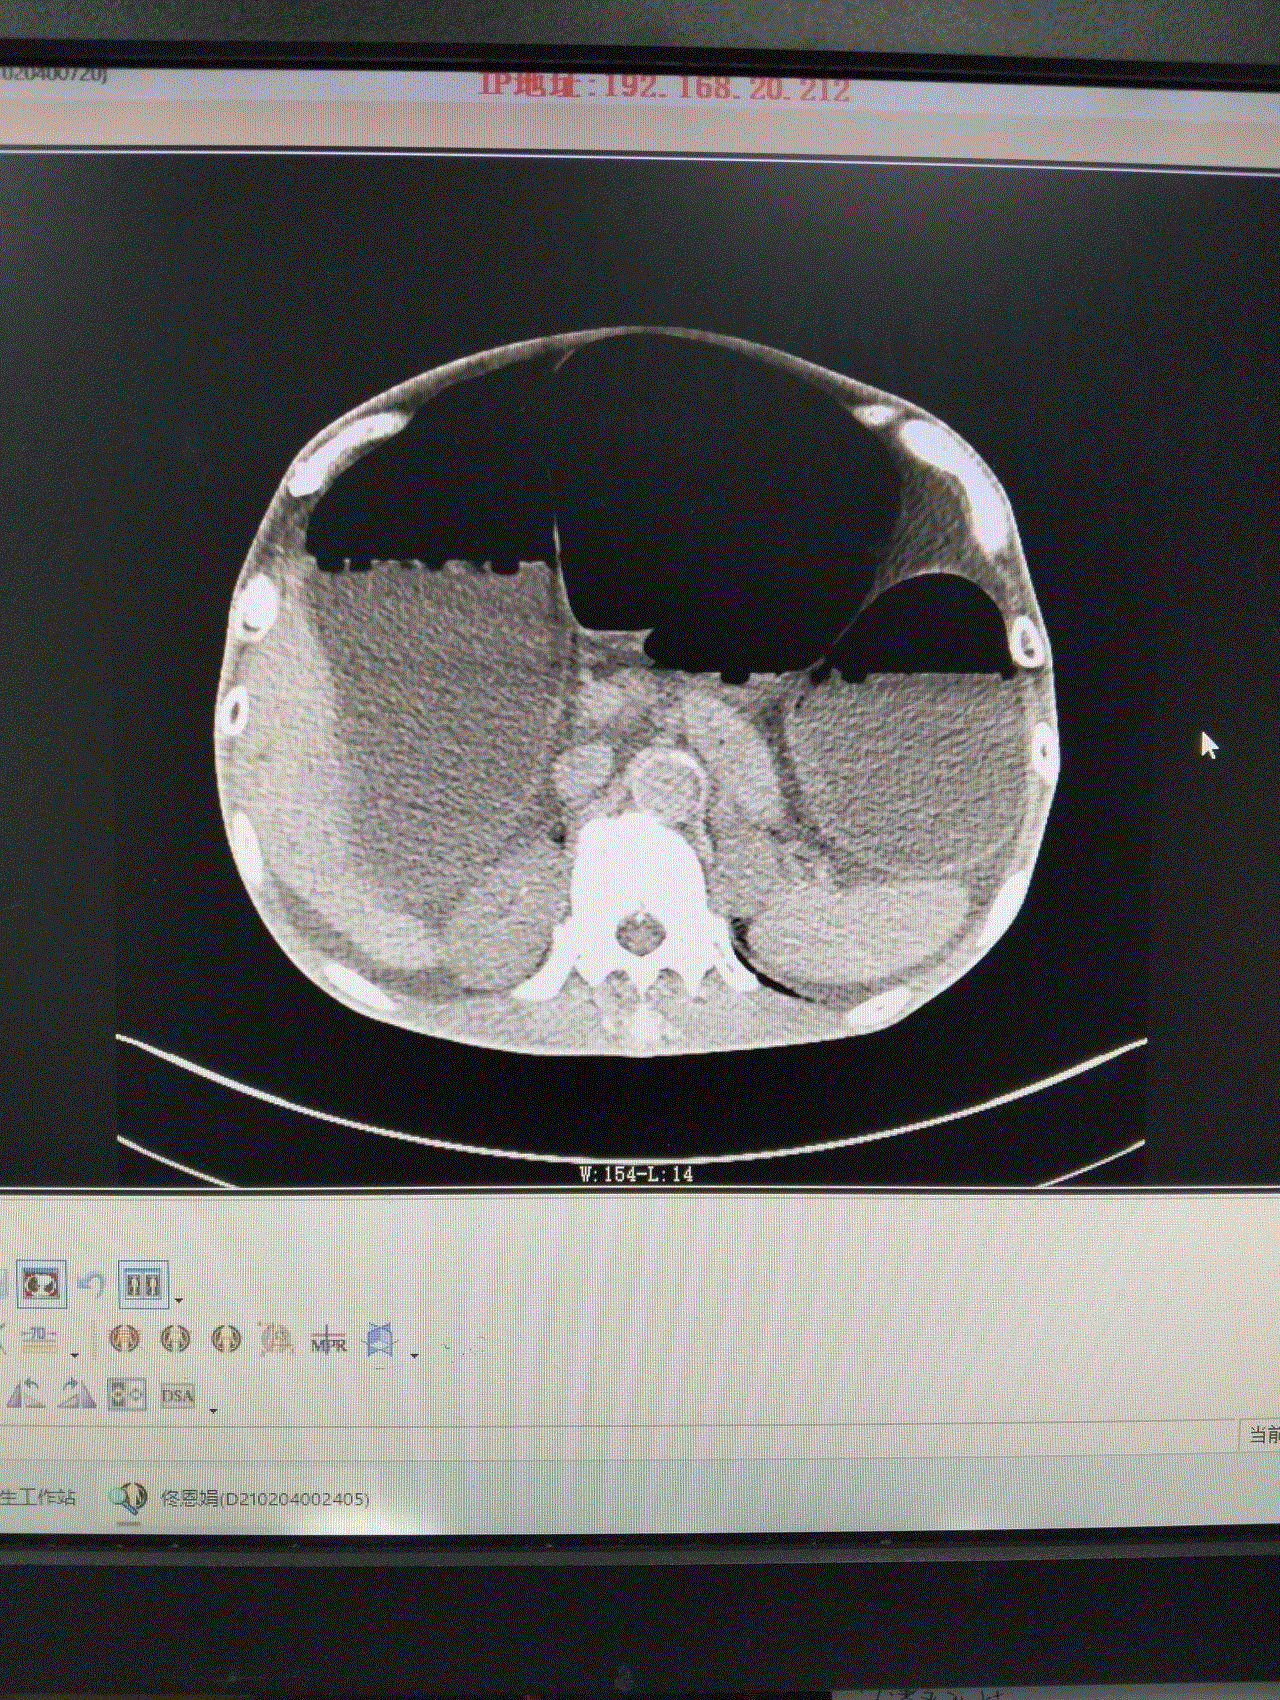

此时的龚大爷,腹部高高隆起,犹如临产的孕妇,叩诊鼓音明显,情况危急!CT显示,龚大爷的结肠严重扩张,脏器被挤压移位。若不及时解除梗阻,随时可能引发腹膜炎、感染性休克,甚至危及生命。然而,常规胃肠减压对低位肠梗阻效果有限,治疗陷入僵局。